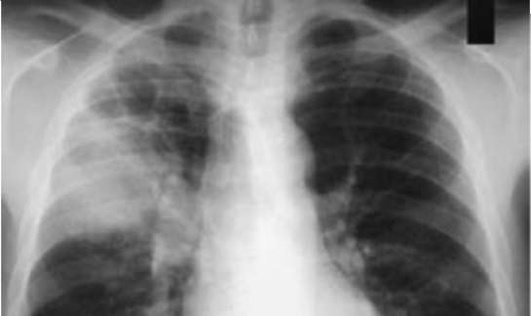

При этом следует исключить кашель, связанный с привычной аспирацией пищи вследствие дисфагии, - наиболее частую причину затяжного кашля у грудных детей, вскармливаемых как грудью, так и искусственно. Дисфагия может быть следствием пареза мягкого нёба, глоточной мускулатуры, а также незрелости глотательного рефлекса. Аспирация пищи происходит либо во время ее приема, либо позже, при желудочно-пищеводном рефлюксе. Рефлюкс без дисфагии обычно не сопровождается поражением глубоких отделов дыхательных путей. Аспирация ведет к химическому повреждению слизистой оболочки бронха, развитию бронхоспазма, размножению бактериальной флоры (часто кишечной), развитию пневмонии. Установление факта дисфагии требует обычно наблюдения за процессом кормления, поскольку не всякая мать фиксирует внимание на связи кашля с приемом пищи. Помимо «поперхивания», «закашливания» во время еды, для аспирации пищи характерно появление хрипов, которые быстро исчезают или меняют свою локализацию и интенсивность после кашлевого толчка. При рефлюксе отмечается кашель после срыгивания, часто ночью. Признаки бронхита обычно появляются с 1-го месяца жизни, иногда после ОРИ, с умеренной одышкой, часто удлиненным выдохом, рассеянными сухими и влажными хрипами, глубоким, продуктивным кашлем. Бронхитические явления часто непостоянны. На этом фоне может определяться участок укорочения перкуторного звука и локальных хрипов (в 70% над правой верхней долей) (рис. 16.4).

pic 0065

Рисунок 16.4Рентгенограмма при аспирационной пневмонии